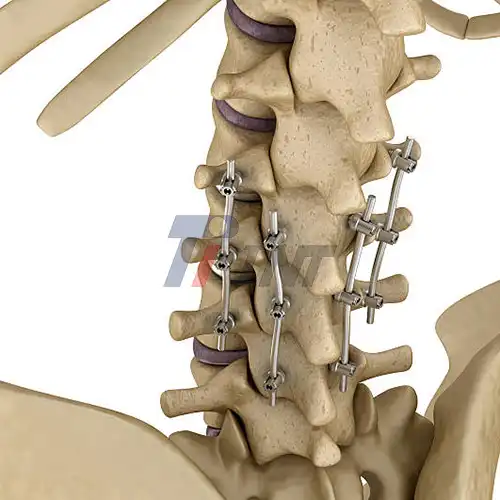

2025-10-10 08:47:05How Titanium Rods Improve Spinal Fusion and Fracture Recovery?